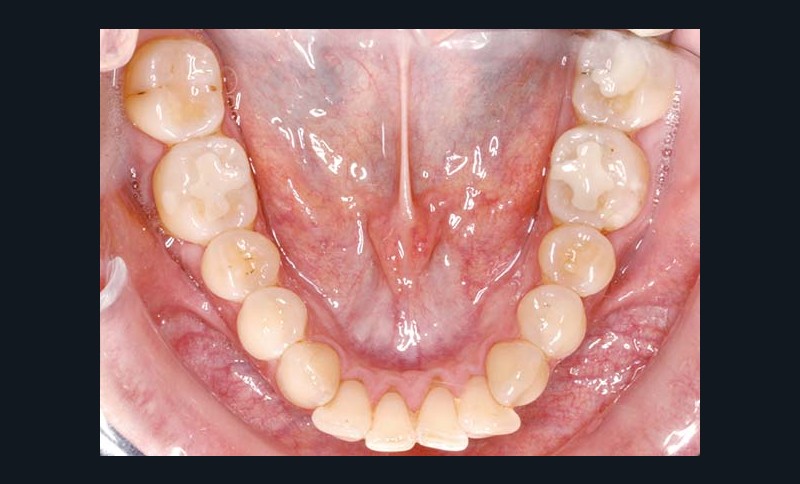

La patiente âgée de 40 ans présente une classe II bilatérale associée à une dysharmonie dento-maxillaire modérée et à une supraclusion de 50 %.

Sur le plan squelettique, les bases osseuses sont en classe II (ANB = 5°) et en bi-rétroposition (SNA = 78°, SNB = 73°). Au niveau des tissus mous, la patiente montre un profil labial concave, une rétrogénie et une distance cervico-mentonnière courte. Les tissus sous-mentonniers sont affaissés et l’angle naso-labial est de 90° (fig. 1 à 9).

Après évaluation parodontale permettant d’exclure toute contre-indication opératoire, les appareillages orthodontiques sont mis en place en technique vestibulaire bidimensionnelle (slots 018 incisifs et 022 postérieurs) : Clarity™ (3M Unitek) au maxillaire et Mini-Diamond™ (Ormco) à la mandibule. Des arcs 014 NiTi sont initialement mis en place.